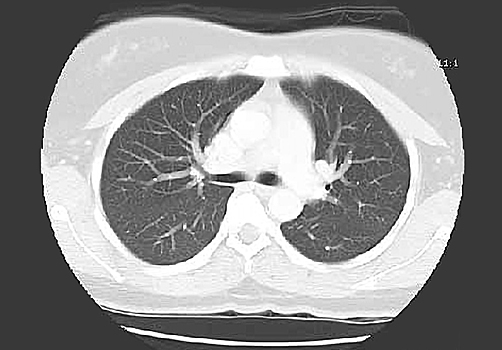

Исследователи научили программу находить ранее незаметные изменения в изображениях с компьютерной томографии (КТ). Она сравнивает первые такие изображения, полученные при диагностике рака, и те, что сделали после первых двух-трёх циклов иммунотерапии.